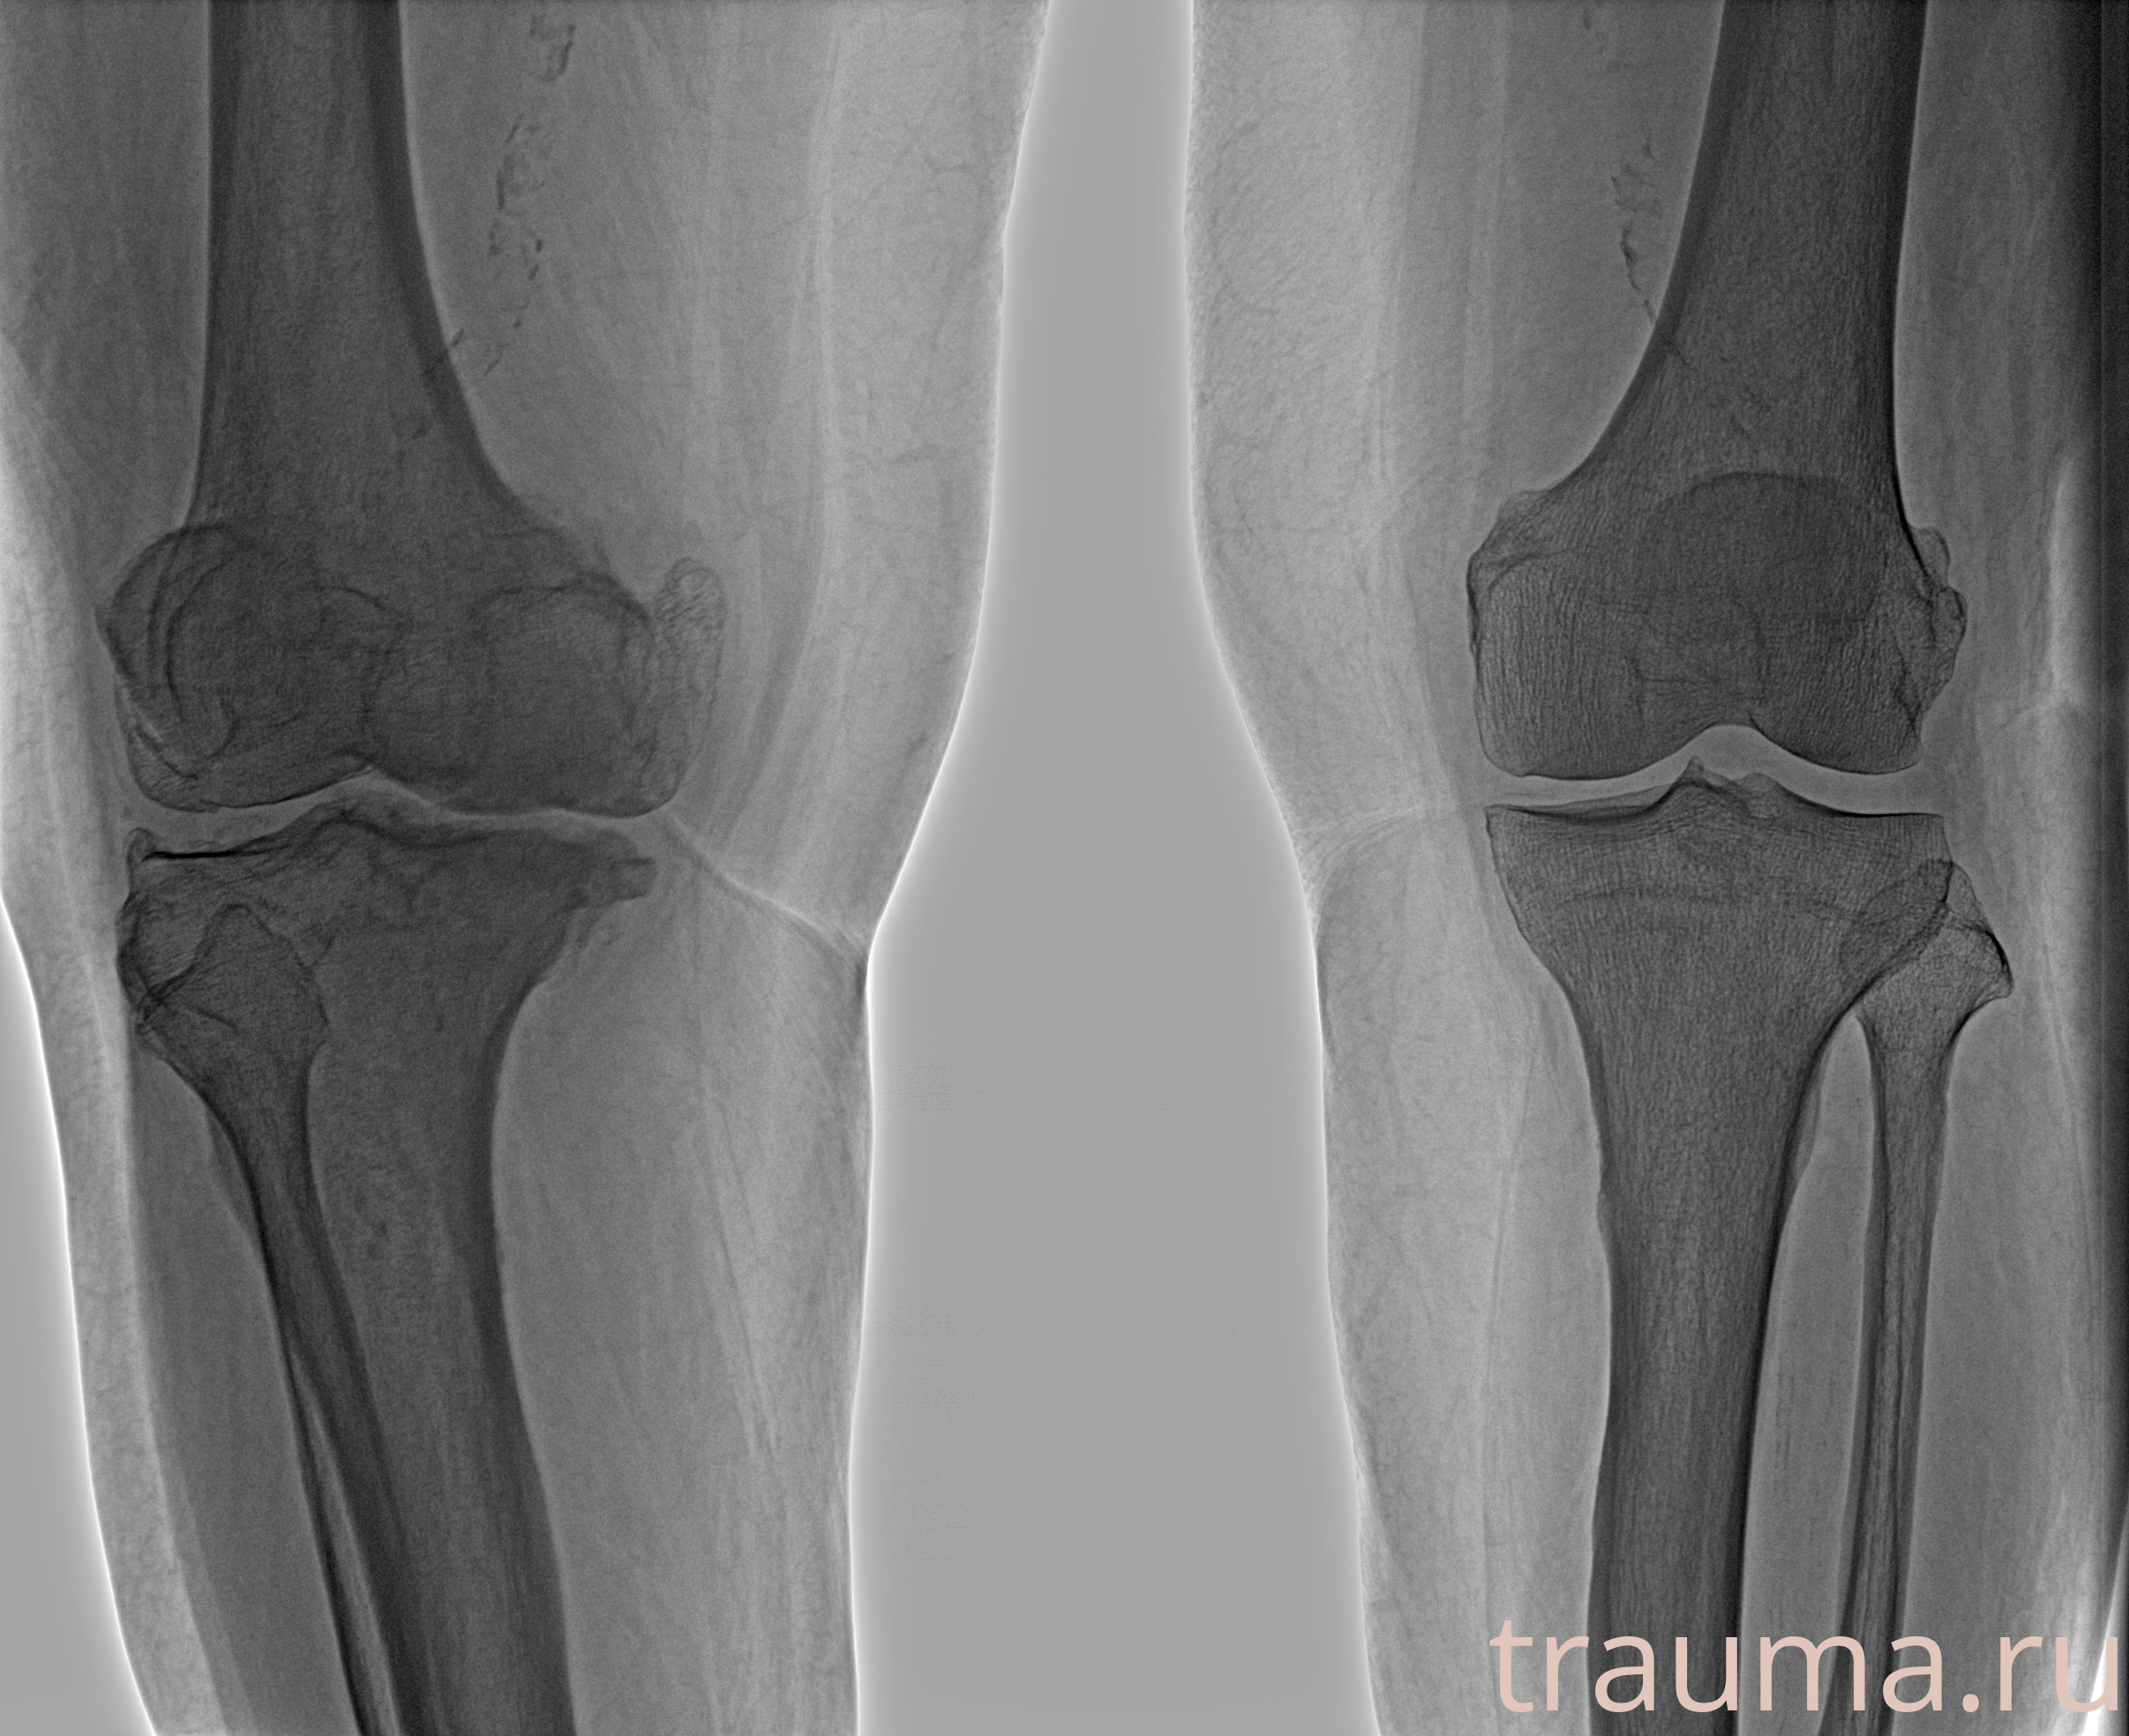

Рентген на дому: по вашему адресу приезжает врач-рентгенолог, травматолог-ортопед с мобильным рентгеновским аппаратом, проводит диагностику травмы или заболевания, делает необходимые рентгенограммы, дает рекомендации по дальнейшему лечению. Получить качественные снимки в домашних условиях возможно благодаря уникальной методике, разработанной МосРентген Центром для института  Склифосовского